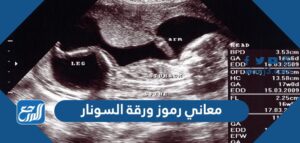

معاني رموز ورقة السونار

يحتوي جهاز السونار على العديد من الرموز الضرورية والتي تعبر عن معاني هامة جدًا، وتظهر هذه المعاني جميعًا في الآتي:[1]

- BPD: ويُستخدم هذا المعني لتوضيح عمر الجنين، وكذلك التطور الطبيعي الخاص به، وهل هذا الجنين ينمو بشكل طبيعي أم بشكل غير طبيعي، إذ تتم طريقة القياس من خلال وضعه بين جانبي رأس الجنين، وتكون القياسات طبيعية إذا وصلت إلى 2.4 سم إلى 9.5سم في الأسبوع الثالث عشر من الحمل.

- CPR: يوضح هذا المعني النسبة البسيطة جدًا بين نبض الشريان الدماغي الأوسط، وبين نبض شريان المشيمة، خاصة وأنه يعبر عن النسبة الغير طبيعية للجنين وذلك في حالة نتائج الحمل السلبية.

- CRL: يوضح هذا الرمز تحديد الترتيب الطبيعي بين الجنين والجنين الآخر بشكل أكثر دقة ووضوح، ويتم ذلك من خلال قياس انحناءات الجنين من ناحية الأعلى ومن ناحية الأسفل، خاصة وأن الجنين يكون على شكل حرف C.

- DICOM: يساعد هذا الرمز في عملية التعامل مع معلومات وبيانات التصوير المختلفة الموجودة على جهاز السونار، ويفيد ذلك في عملية تخزين هذه المعلومات وطباعتها وحتى نقلها.

- FL: يساعد في التعرف على عمر الجنين وحجمه بشيء من التفصيل، خاصة وأن هذا الرمز يساعد في قياس طول الفخذين عند الجنين، محيط الرأس، ومحيط البطن للتعرف بدقة عالية على نمو الجنين الطبيعي.

- FLDA: يتم اللجوء إلى هذا الرمز في النصف الثاني والثالث فقط من الحمل، خاصة وأنه يساعد في التعرف على تقييم نمو الجنين، وهل يتم بصورة طبيعية أم هناك مشكلات تعيق ذلك الأمر.

- HC: ويساعد هذا الرمز في قياس محيط الرأس للجنين، ومن ثم إمكانية التعرف بسهولة على النمو الطبيعي لهذه المنطقة من جسم الجنين، ويتم اللجوء إلى هذا الرمز فقط في الثلث الثاني من الحمل.

- GS: يساعد في قياس كيس الحمل الخاص بالجنين، إذ يسهم ذلك في التعرف على غرف القلب، الأوعية الدموية، المثانة، الحوض الكلوي، المرارة، والمعدة، كما يمكن اللجوء إليه لتحديد تشوهات الجنين الخلقية خاصة في الأيام الأولى من الحمل.

- LAD: يعبر هذا الرمز عن تحليل التمايز الخطي الذي يوضح البيانات الطولية لهذا الجنين.

- MSD: يساعد في التعرف على متوسط قطر كيس الحمل خاصة في في الأسابيع الأولى.

- MYD: يساعد في قياس متوسط قطر كيس الصفار، إذ يعبر وجود هذا الرمز على موت الجنين أو على وجود تشوهات خلقية.

- STIC: يساعد هذا الرمز في تحليل قلب الجنين للكشف عن ما به من أمراض، ويمكن القيام به من خلال مسح الحجم بطريقة تلقائية أو من خلال تحليل بيانات الصورة الخاصة بالجنين والموجودة على جهاز السونار.

- TVS: يعبر هذا الرمز عن الفحص المهبلي خاصة وأنه يتم وضعه داخل المهبل ليعبر بشكل أكثر دقة عن الأعضاء المهبلية التناسلية.

- Top: ويعبر ذلك عن انتهاء فترة الحمل وحاجة الأم إلى الولادة في أسرع وقت ممكن.